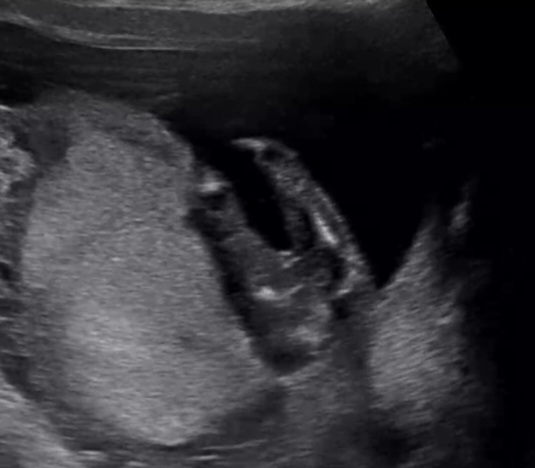

안녕하세요 애기 성별로 병원다녀왔는데 애매하다고 하셔서 ㅜㅜ 저는 딸같은데 혹시 어떻게.보이시나요 14주차입니다

미사일은 안보이는데 삼각점이 보이는것 같아서..애매하다고 하신것 같은데..조심스레 아들일수도 있을것 같아요 ~

딸같은데 14주는 좀 많이 이르네용 ㅎㅎ 16주 기형아 하시면서 보시고 20주에 정확히 받아보세용~~

딸은 20주되야 확정이에욥 전 병원에서 애매하다하구 다음에 가서 아들 확정 받았어욥